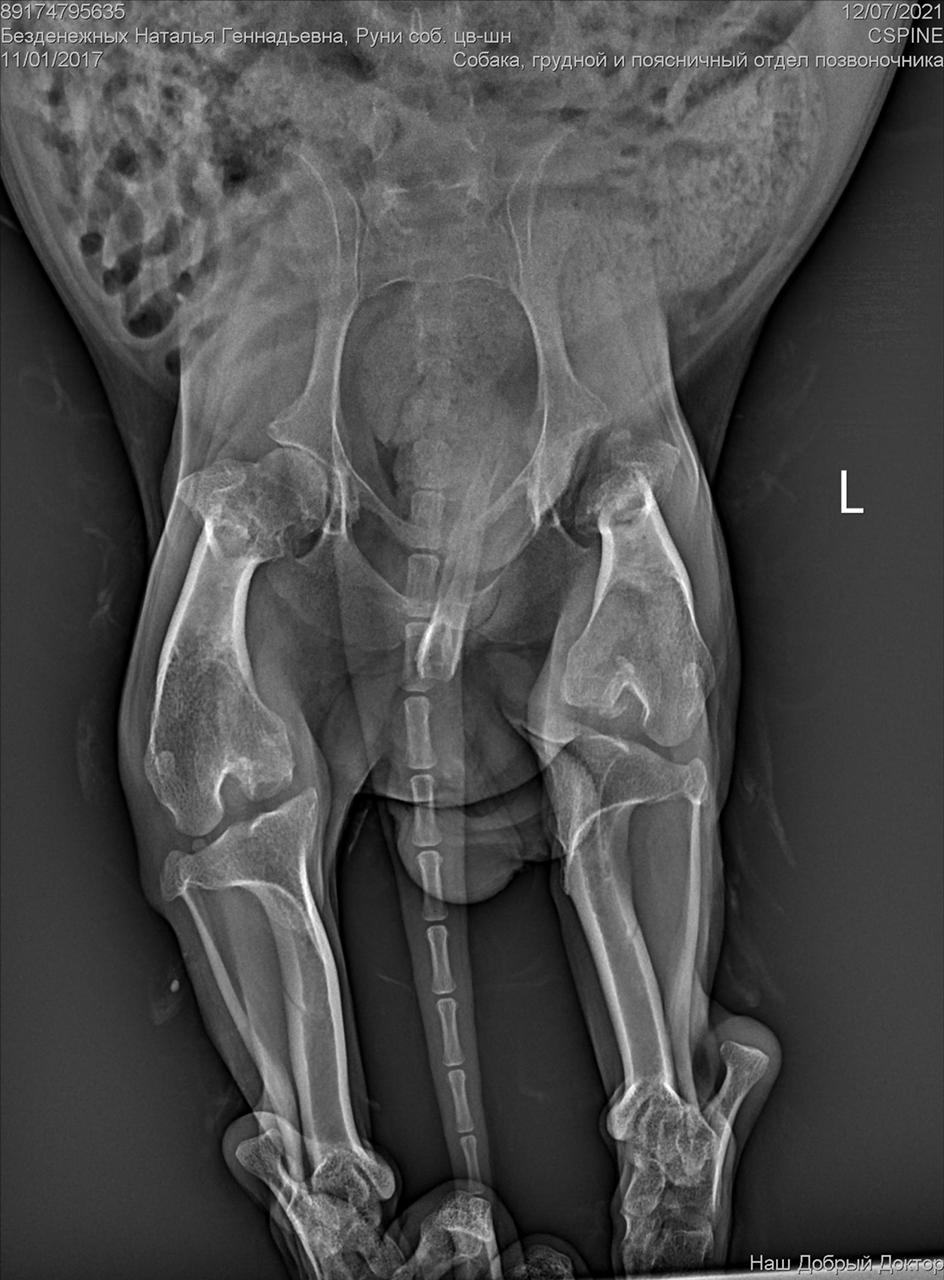

С собакой сегодня поедут в клинику. Передержать и полечить смогут. Попросила в клинике посмотреть клеймо и посканировать ип.

ПОнадобится наша помощь с оплатой лечения и поиском дома.